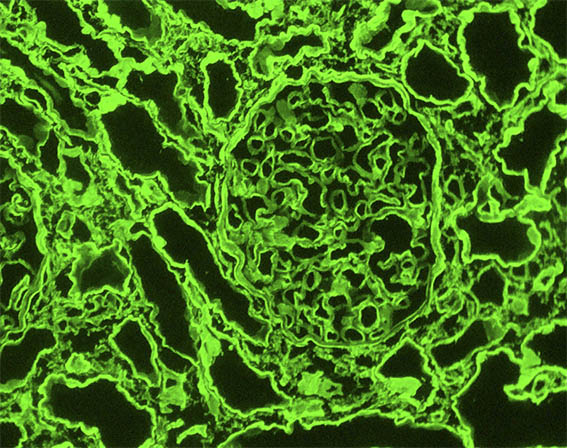

Figura 11. Inmunofluorescencia directa para IgM, X400.

Figura 12. Inmunofluorescencia indirecta para la cadena alfa-1 (MAB1) del colágeno tipo IV, X400.

Figura 13. Inmunofluorescencia indirecta para la cadena alfa-3 (MAB3) del colágeno tipo IV, X400.

Figura 14. Inmunofluorescencia indirecta para la cadena alfa-5 (MAB5) del colágeno tipo IV, X400.

Figura 15. Control positivo (en riñón normal) para cadenas alfa-3 (MAB3 - izquierda) y alfa-5 (MAB5 - derecha) del colágeno tipo IV, X400.

Inmunofluorescencia para IgA, IgG, C3 y C1q: Negativas.